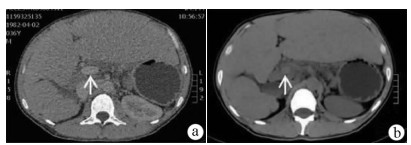

Expert consensus on the imaging diagnosis of hepatic echinococcosis

Radiology of Infection Sub-branch, Radiology Branch, Chinese Medical Association, Committee on Radiology of Infectious, Radiology Branch, Chinese Medical Doctor Association

2021, 37(4): 792-797. DOI: 10.3969/j.issn.1001-5256.2021.04.014

Abstract(1244) HTML (604) PDF (2065KB)(121)

Abstract:

Echinococcosis is a zoonotic disease with global distribution and has become an issue seriously affecting public health around the world. Imaging technology plays an important role in the early diagnosis, preoperative evaluation, and treatment outcome monitoring of hepatic echinococcosis. At present, no consensus has been reached on the imaging diagnosis of echinococcosis, which brings difficulties in the learning and training of imaging professionals and the standard diagnosis and treatment of echinococcosis in clinical practice. For this reason, Beijing YouAn Hospital, Capital Medical University, and The First Affiliated Hospital of Xinjiang Medical University organized the radiologists engaged in infection and inflammation from several hospitals to reach a consensus on the basis, principles, and criteria for the imaging diagnosis of echinococcosis and the differential diagnosis of echinococcosis, with reference to international guidelines, related articles, the latest research findings in China and globally, and the methodological requirements for the establishment of guidelines and standards in evidence-based medicine, so as to provide a clear diagnostic basis for clinicians in the clinical application of hepatic echinococcosis imaging.